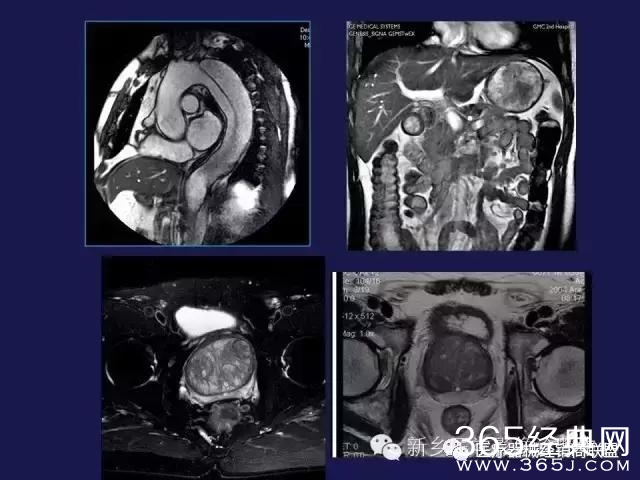

CT、MRI很难?NO,今日我们一起来学习一下如何读CT、MRI!

内行看门道: